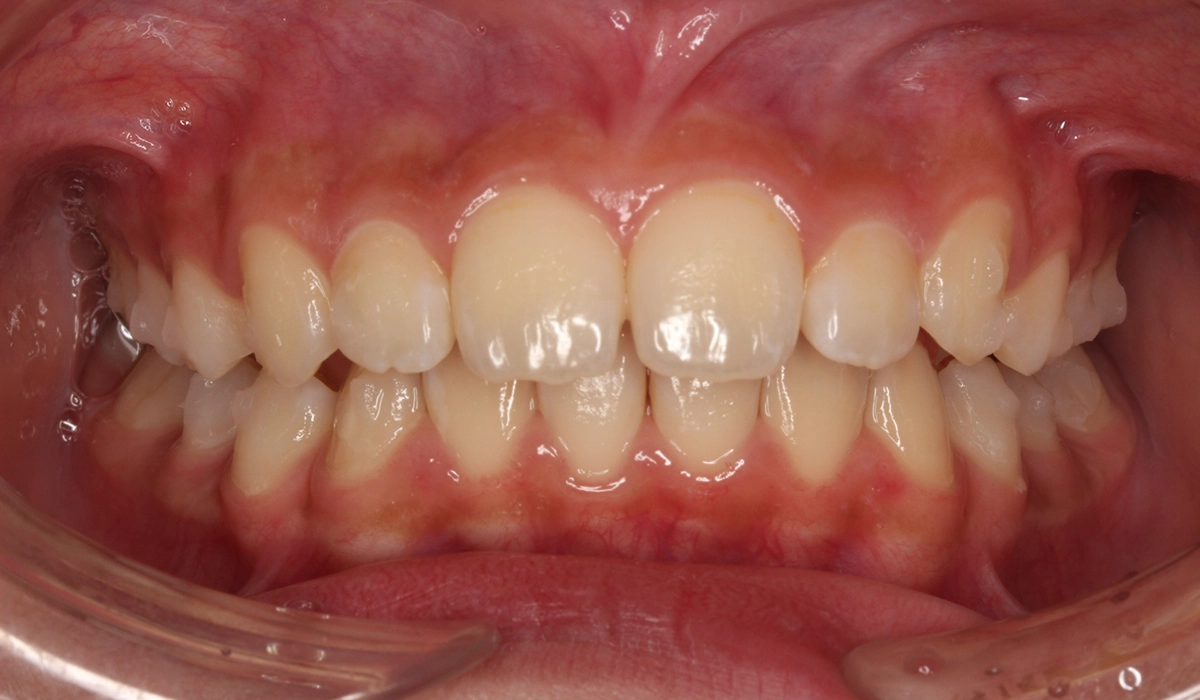

術前:正面

術後:正面